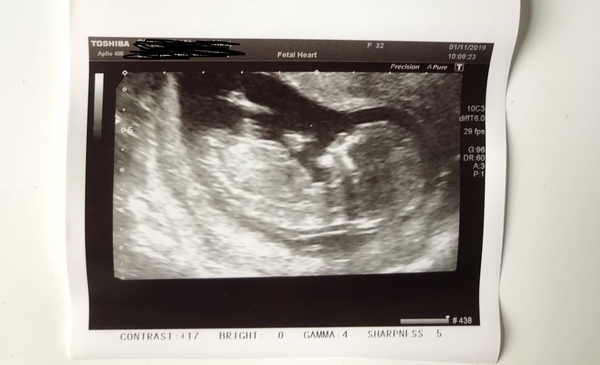

Herewego2020 · 01/11/2019 16:31

@facevalue my partner just goes "get the scan pics of the boys out the cupboard now so I can compare" it's fun guessing lol. My boys told me it has to be a girl though so no pressure 😳lol

More lovely scan photos, congrats and happy Friday everyone!

Had a fab scan, baby was jumping all over the place. I’ve been put forward a few days and due date is now 10th May. Guesses anyone?

Lovely to see all the pics and congrats to all. @Allyism @facevalue @Herewego2020 all I am seeing are beautiful girls! 💗

@allyism I am saying girl :)